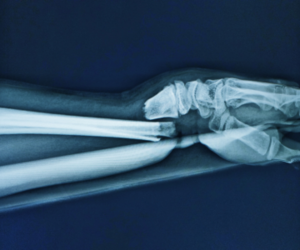

Bone Fracture - Dr. Pramod Kumar Surve

Dr. Pramod Kumar Surve is a renowned Orthopedic surgeon specializing in Orthopaedic Surgery, Spine Surgery, Trauma Surgery, and Joint Replacement. ...